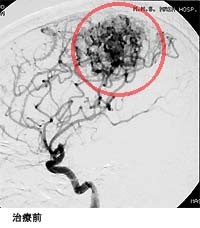

脳出血による半身麻痺と意識障害で発症した患者さまの治療前後の血管撮影を下に示します。(赤線内が脳動静脈奇形の部分)